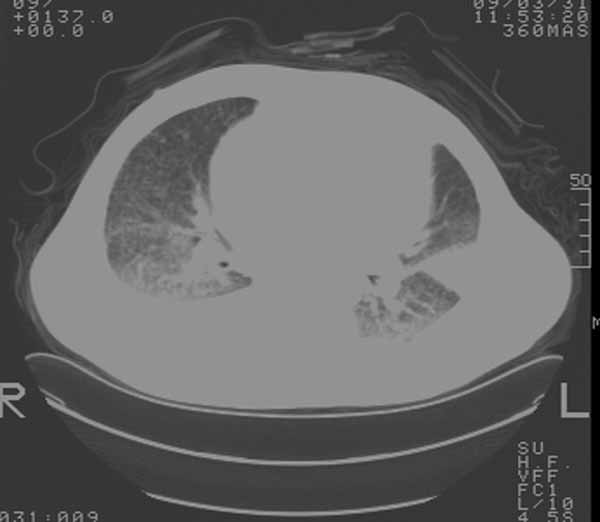

以下是引用余辉在2009-3-31 18:43:00的发言:[br]肺水肿,双侧心腔积液,心包积液,心影增大,疑似心衰

以下是引用wangyong1977在2009-3-31 20:46:00的发言:[br]肺水肿,双侧胸腔积液,心包积液,心影增大,疑似心衰 [br]

以下是引用宇宙ct在2009-3-31 18:57:00的发言:[br]肺水肿,双侧心腔积液,心包积液,心影增大,疑似心衰 [br] [br]